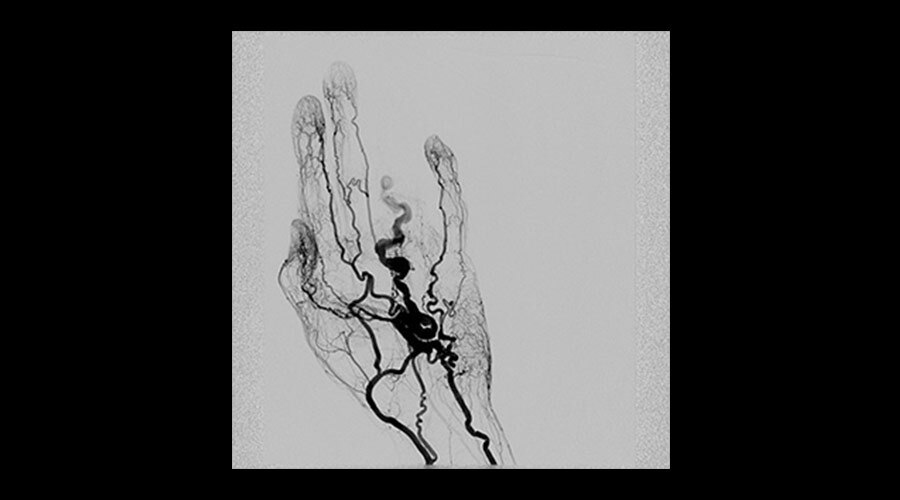

-

Elde AVM